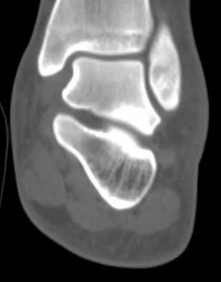

Figures 3a through 3h

1

Normal foot

2

Calcaneonavicular (CN) coalition

3

Talocalcaneal (TC) middle facet coalition

4

TC posterior facet coalition

- TC posterior facet coalition

Figure 3a shows a flatfoot. Figure 3b shows an MF and TB, but not a C sign. Figure 3c shows a bony irregularity between the calcaneus and the navicular and a WN. Figure 3d shows an MF. Figure 3e shows an MF, but narrowing or loss of the posterior facet. Figures 3f through 3h show medial edema and joint irregularities consistent with a posterior facet coalition.